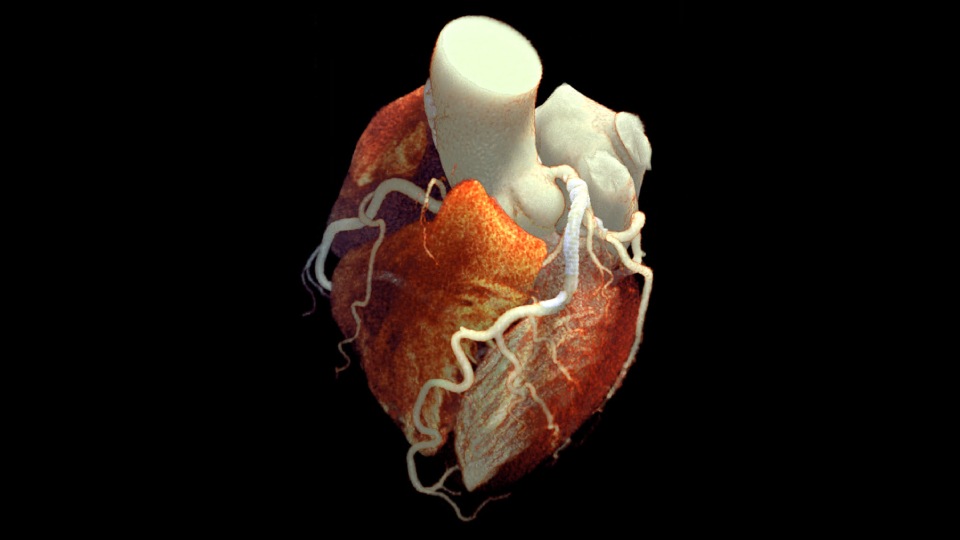

Die kardiologische Bildgebung erweitern und verbessern

Erweitern Sie die routinemäßige kardiologische Bildgebung durch die zusätzlichen klinischen Erkenntnisse der Spektraldetektor-CT für moderne kardiologische Anwendungen.